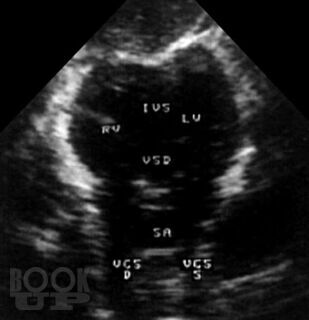

В атласе на большом числе богато иллюстрированных примеров дана эхо- и допплеркардиографическая картина врожденных пороков и ряда заболеваний сердца, а также правила применения методики ультразвукового исследования. Издание восполняет дефицит информации об ультразвуковой диагностике многих сложных врожденных пороков сердца и возможности оценки состояния больных после хирургической коррекции порока.

При подготовке атласа сотрудниками Научного центра сердечно-сосудистой хирургии им. А.Н. Бакулева РАМН (директор – академик РАМН Л.А. Бокерия) использован опыт ультразвукового исследования больных с пороками и заболеваниями сердца (более 60000 пациентов), обследованных в Центре за период с 1976 по 2003 г.